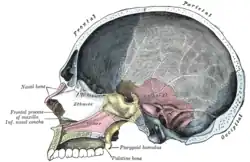

Le crâne de face. Coupe sagittale du crâne.

Coupe sagittale du crâne. Toit, plancher et paroi latérale de la cavité nasale gauche.